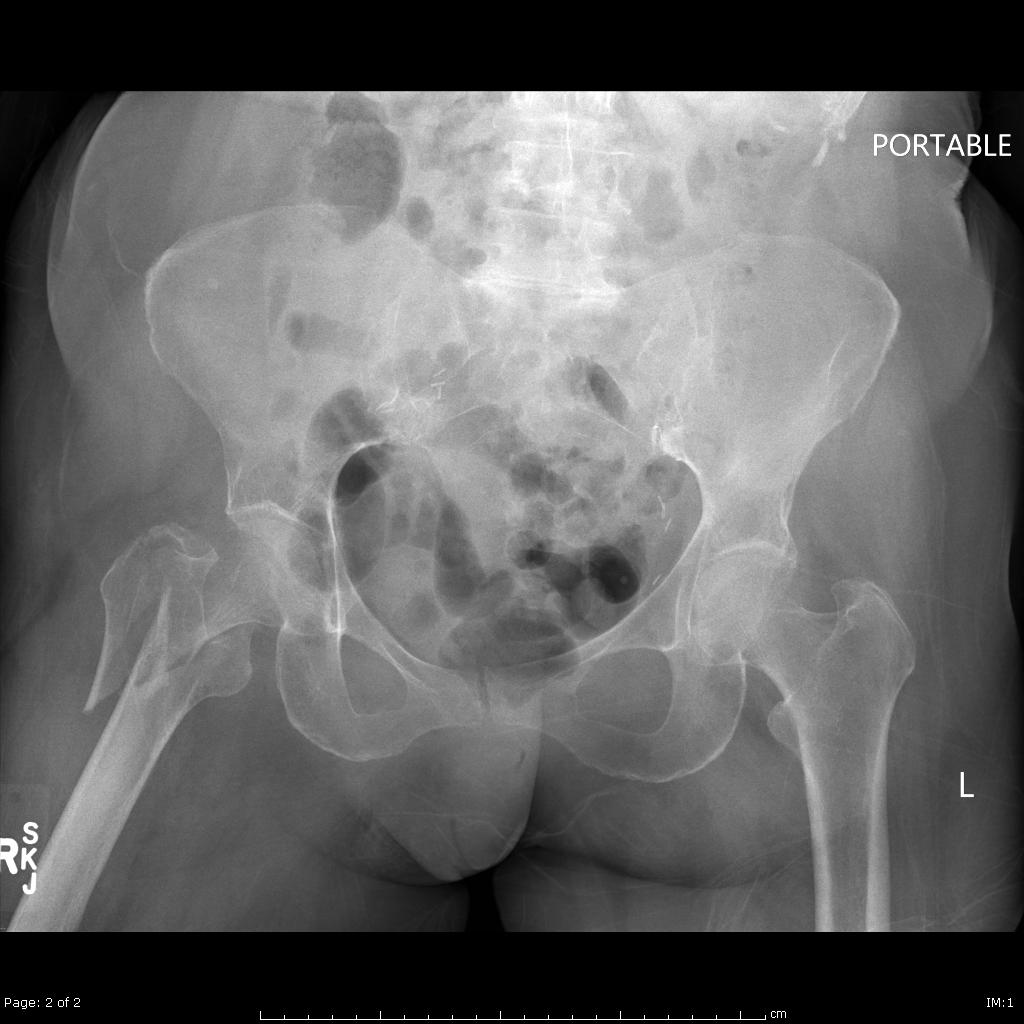

535 fractures of hip and pelvis with mcc 536 fractures of hip and pelvis without mcc 791 prematurity with major problems 793 full term neonate with major problems 963. It covers icd codes 800 to 999. Pcp codes a subsequent fracture encounter.

Diseases of the digestive system. The icd code s720 is used to code hip fracture a hip fracture is a serious femoral fracture that occurs in the proximal end of the femur (the long bone running through the thigh), near the hip. Search about 41 items found relating to hip fracture

821 fracture of other and unspecified parts of femur; The icd code s720 is used to code hip fracture a hip fracture is a serious femoral fracture that occurs in the proximal end of the femur (the long bone running through the thigh), near the hip.